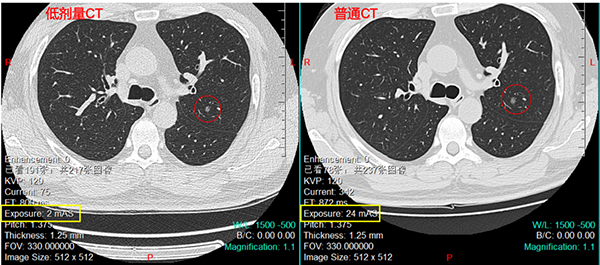

低剂量CT即放射量低于普通CT的扫描。由于肺组织为含气器官,X线透过率较高,因此可以用较小的射线量,得到清晰的肺部图像。

从上图两种CT扫描对比看,低剂量CT图像看起来锐度更高、颗粒感更强,但对于左肺上叶的病变的观察与普通CT并无太大区别。而射线暴露量约为普通CT的1/10。